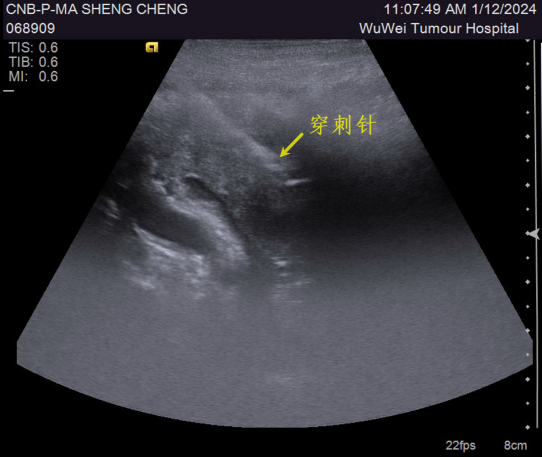

胰腺肿物穿刺活检

胰腺肿物 超声引导下穿刺活检